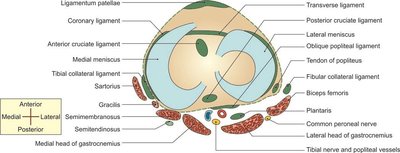

Tibial (medial) collateral ligament: Provides medial stability.

Fibular (lateral) collateral ligament: Provides lateral stability.

Oblique and arcuate popliteal ligaments: Reinforce the posterior aspect.

Transverse ligament: Connects the menisci.

Lateral bursae: Located near the lateral head of gastrocnemius, fibular collateral ligament, biceps femoris, popliteus tendon.

Medial bursae: Near the medial head of gastrocnemius, anserine bursa, tibial collateral ligament, semimembranosus.

Relations of the Knee Joint

The knee joint is surrounded by various muscles, tendons, nerves, and vessels, which are important for its function and clinical assessment.

Posterior: Popliteal vessels, tibial nerve, heads of gastrocnemius.

Medial: Sartorius, gracilis, semimembranosus, tibial collateral ligament.

Nerve Supply

The knee joint is innervated by branches of the femoral, tibial, and common peroneal nerves, which are important for movement and pain sensation.

Femoral nerve

Tibial nerve (branch of sciatic)

Common peroneal nerve (branch of sciatic)